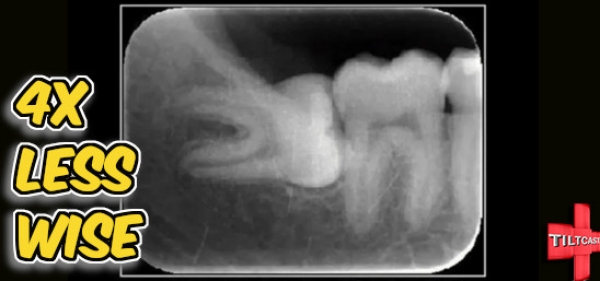

S16 EP 630 4X Less Wise